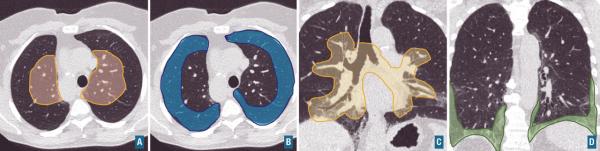

A : zone de distribution centrale, B : zone de distribution périphérique, C. zone de distribution péribronchovasculaire, D : zone de distribution sous-pleurale basale. Lire aussi Article L’apport méconnu des scanners dans l’évaluation de la dénutrition Article Imagerie dans les cancers de l’ovaire Article Web Gonalgie : quand prescrire une imagerie et laquelle ? Article Web La mammographie pour détecter les patientes à risque cardiovasculaire ? Article Douleur thoracique stable : le coroscanner d’abord Article Pneumopathie interstitielle diffuse